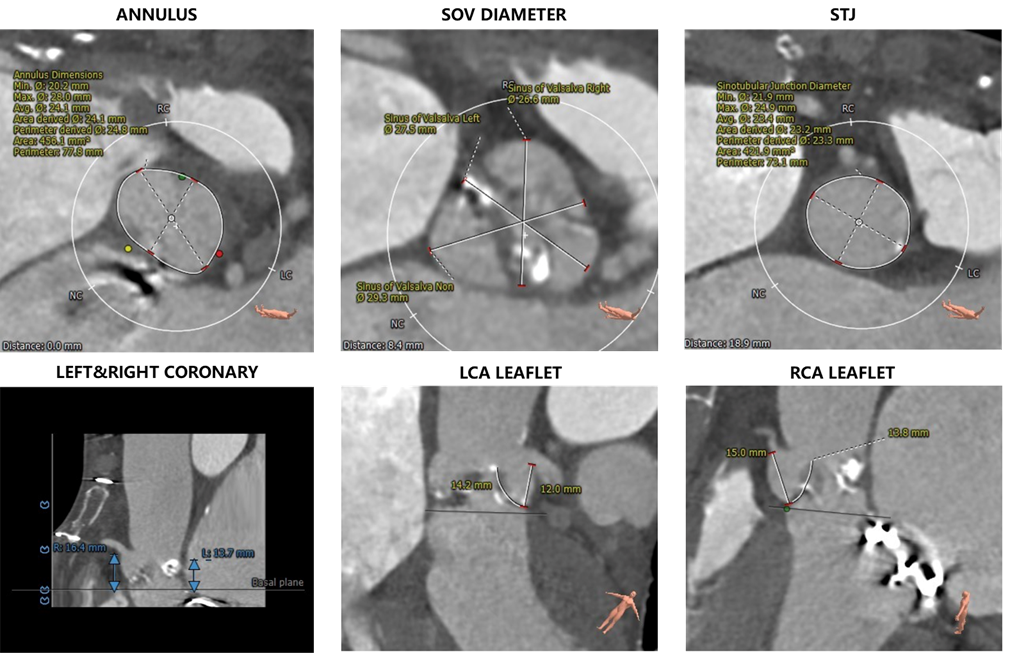

1.主动脉瓣瓣环周长77.8,平均周长径24.1。

2.主动脉瓣成三叶式,瓣叶增厚并伴有四级钙化,钙化分布不均匀,左无交界处钙化融合形似嵴并延伸至血管壁。

3.左右冠脉开口高度可,冠状动脉钙化严重。

4.心脏增大伴左心室壁增厚,左心耳部血栓形成,二尖瓣机械瓣植入,心包少量积液。

1.瓣叶钙化并纤维化增厚对人工瓣膜形态存在影响,左无冠窦交界处钙化为根部最大影响因素。

2.根据CT分析钙化分布、瓣叶长度及瓦氏窦宽度预估左冠存在遮挡可能性。

主动脉根部评估:

瓣环上解剖结构评估: